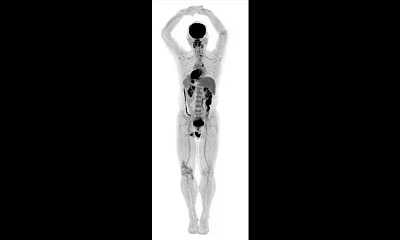

New York, Nov 20 (IANS) The world's first medical imaging scanner that can capture a 3D picture of the entire human body at once in as little as 20-30 seconds has produced its first scans, say scientists, noting that the technology can aid in improving diagnostics to tracking disease progression to researching new drug therapies.

Called EXPLORER, the scanner combines positron emission tomography (PET) and x-ray computed tomography (CT) and can produce image up to 40 times faster.

"The level of detail was astonishing... We could see features that you just don't see on regular PET scans. And the dynamic sequence showing the radiotracer moving around the body in three dimensions over time was, frankly, mind-blowing," said Ramsey Badawi, chief of Nuclear Medicine at at the University of California - Davis, in the US.

According to Cherry, EXPLORER will have a profound impact on clinical research and patient care because for the first time, an imaging scanner will be able to evaluate what is happening in all the organs and tissues of the body simultaneously.

The machine can also quantitatively measure blood flow or how the body takes up glucose everywhere in the body.